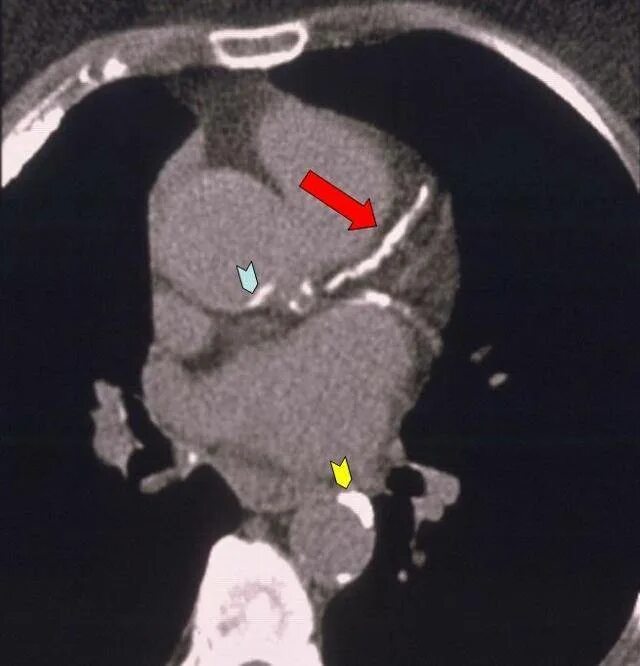

Стенты мрт